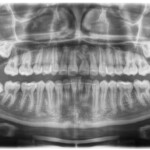

This is an example of a teenage patient with photographs of their smile before and after treatment at Braceline. Our orthodontic treatments are designed to provide maximum results in minimal time and to help you achieve the smile you always wanted!

Before Transformation!